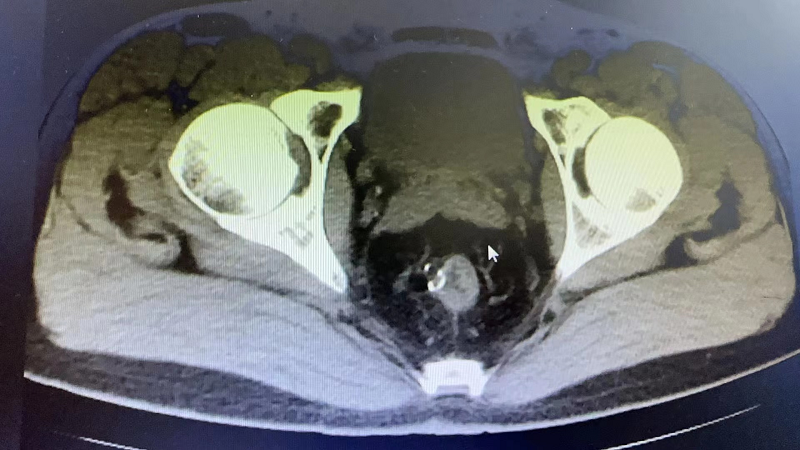

近期,73岁的J大爷比较烦恼,他出现了排尿困难、疼痛症状,这严重影响了J大爷的生活。在家人的陪伴下,J大爷辗转当地多家医院,但都因为J大爷有多种基础疾病未能如愿,最终在亲戚的介绍下来到美高梅app 泌尿外科就诊。通过接诊医生的详细询问病史并结合相关检查,诊断J大爷为:膀胱结石、泌尿道感染,建议J大爷住院行微创手术治疗。

经询问和检查,J大爷有重度贫血、慢阻肺、呼吸衰竭、冠心病支架植入术后等既往病史,泌尿外科高茂主任特邀多个专科主任前来参加会诊,各位专家积极发言,围绕J大爷的基础疾病、手术风险等展开讨论,最后确定适合J大爷的诊治方案。

手术由泌尿外科高茂主任亲自操刀,在麻醉科、手术室的倾力配合下,一小时就为J大爷完成尿道内镜下膀胱结石钬激光碎石术,成功解决了约3.0*2.0cm的大结石。